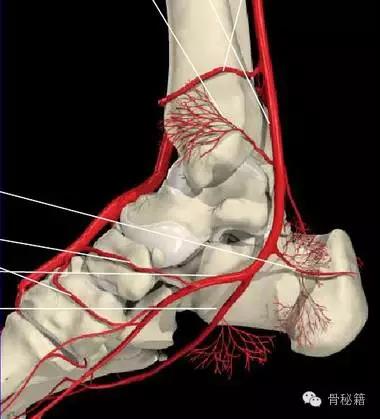

还有一个就是血供的影响距骨很容易坏死就是血供遭到了破坏

相关7个血管:内踝前动脉、胫后动脉、内踝支、跟骨支跗内侧动脉、跖内侧动脉、跖外侧动脉

最主要的血供包括前方胫前动脉内侧胫后动脉外侧腓动脉的分支(跗骨窦)

当发生骨折脱位时,由于位移巨大,导致相应位移的血管损伤、最终导致距骨坏死所以距骨骨折的分型常用Hawkins分型距骨坏死率随分型严重程度逐渐增加